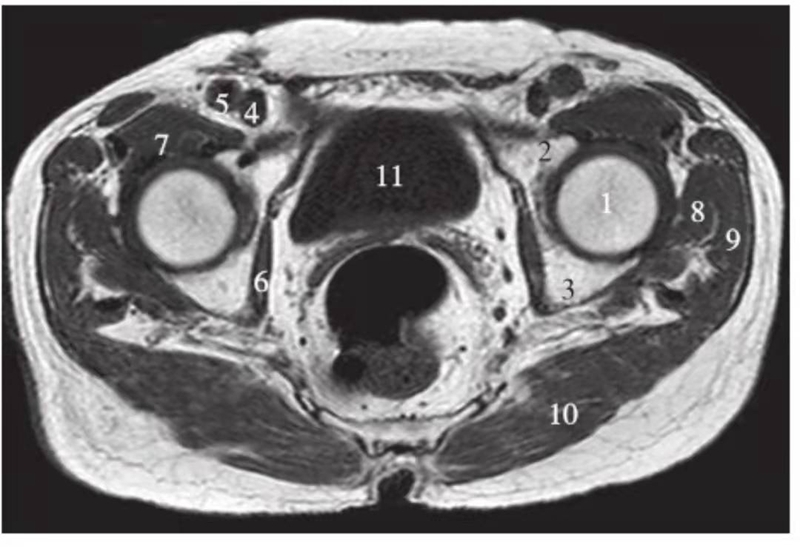

横轴位

正常髋关节股骨头上缘层面T1WI像

1.股骨头;2.耻骨;3.坐骨;4.股静脉;5.股动脉;6.闭孔内肌;7.髂腰肌;8.臀小肌;9.臀中肌;10.臀大肌;11.梨状肌;12.膀胱

正常髋关节经股骨头中心层面T1WI像

1.股骨头;2.耻骨;3.坐骨;4.股静脉;5.股动脉;6.闭孔内肌;7.髂腰肌;8.臀小肌;9.臀中肌;10.臀大肌;11.膀胱